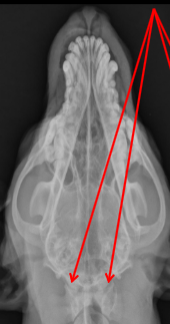

Occipital Condyles